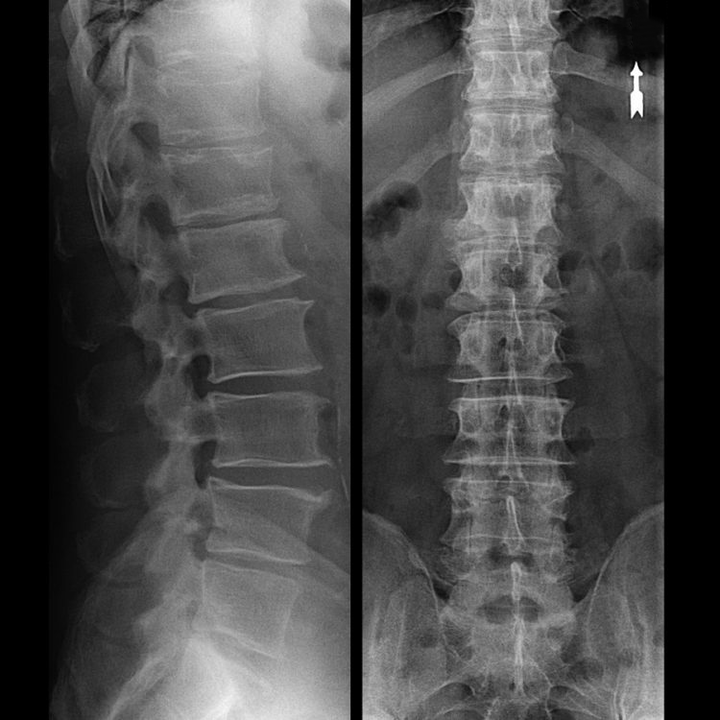

Μια «ακτινογραφία» της αυχενικής μοίρας της σπονδυλικής στήλης και ακόμη και οι λειτουργικές εξετάσεις για κάμψη και επέκταση δεν δείχνουν χόνδρο επειδή ο ιστός του επιτρέπει στις ακτίνες Χ να περάσουν. Ωστόσο, με βάση τη θέση των σπονδύλων, μπορεί κανείς να συναγάγει γενικά συμπεράσματα για το ύψος των μεσοσπονδύλιων δίσκων, τη γενική ανόρθωση της φυσιολογικής καμπυλότητας του αυχένα - λόρδωση - καθώς και την παρουσία οριακών αυξήσεων στους σπονδύλους με παρατεταμένο ερεθισμό των επιφανειών τους από εύθραυστα και αφυδατωμένα μεσοσπονδύλια δισκάκια. Οι λειτουργικές εξετάσεις μπορούν να επιβεβαιώσουν τη διάγνωση της αστάθειας της αυχενικής μοίρας της σπονδυλικής στήλης.

Δεδομένου ότι οι ίδιοι οι μεσοσπονδύλιοι δίσκοι είναι ορατοί μόνο με αξονική τομογραφία ή μαγνητική τομογραφία, η μαγνητική τομογραφία και η αξονική τομογραφία ακτίνων Χ ενδείκνυνται για την αποσαφήνιση της εσωτερικής δομής του χόνδρου και των σχηματισμών όπως εξογκώματα και κήλες. Έτσι, με τη βοήθεια αυτών των μεθόδων γίνεται ακριβής διάγνωση και το αποτέλεσμα της τομογραφίας αποτελεί ένδειξη και μάλιστα πραγματικό οδηγό για τη χειρουργική αντιμετώπιση μιας βουβωνοκήλης στο νευροχειρουργικό τμήμα.